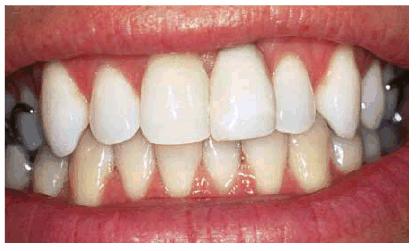

either on an individual tooth or on all teeth (Figures 16-1A, and 16-1B). There are many causes and

Figure 16-1A: An otherwise attractive smile is marred by discolored teeth.

Figure 16-1B: After tooth lightening, the smile is much more pleasing.